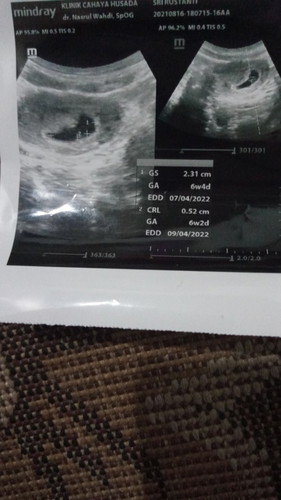

aku darahnya pas di usia 6w kaya awal2 mau haid jadi darah yg coklat campur sama drah kepink2an di pakein softek cuma sehari itu aja banyaknya , kesini2nya flek sedikit kadang flek kdg engga , kt doktr kandungan ku sih kalo masih flek hrus ttp bedrest mengurangi aktftas hrus minum penguat juga biar janinnya kuat ,bund udah usg lagi belum dikhmilan yg 8w nya ?